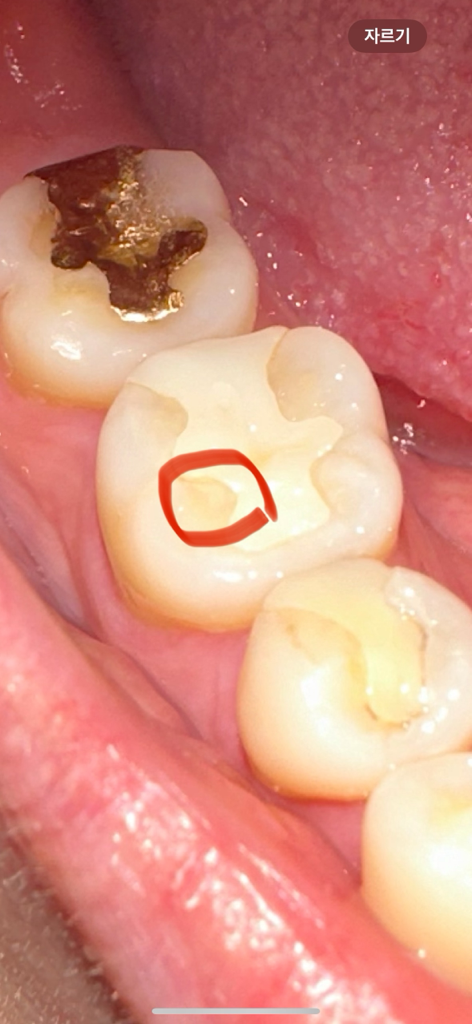

위에 사진이 진료 전 밑에 사진이 진료받은 후 사진입니다 빨간 동그라미 부분 보시면 원래는 저렇게 동그랗게 살짝 파이지않았습니다 보철물이랑 치아 사이 틈이 생긴것같아 전체적으로 다듬어주셨는데 멀쩡한 부분까지 다듬어줬어요.. 이게 올바른진료가 맞나요? 저 부분은 치료를 원하지않았는데 다듬는다는게 이렇게 살짝 파일수도있나요? 전문가분들 도와주세요 ㅠㅠ 다른치과 방문해봐야하나요?